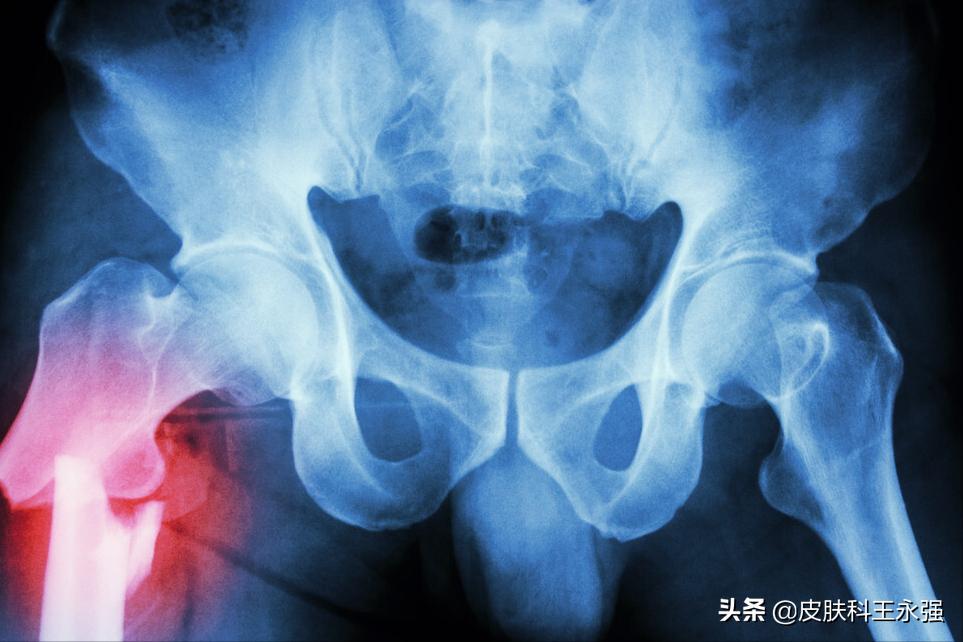

医生了解了小赵的基本情况,为小赵进行了体格检查还开具了臀部X线检查和神经肌电图检查。小赵积极配合做完检查后,医生确定表示,

股骨颈骨折需要有明显的外力冲击导致,而且在髋关节X线检查时,也提示出有明显的骨折现象,臀中肌损伤则没有。